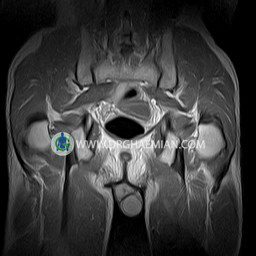

پزشکان اغلب از تصویربرداری ام آر آی برای تشخیص و درمان عارضه های پزشکی که فقط با استفاده از اشعه ایکس یا میدان مغناطیسی و امواج رادیویی قابل مشاهده است، استفاده می کنند. دستگاه ام آر آی تصاویر دقیق از ساختار های داخلی بدن ایجاد می کند. در این کیس استئومیلیت لگن، آتروز و سنیویت دیده می شود.

HIP JOINT MRI

( without contrast )

Technique : coronal STIR , coronal T2 , Axial T1 , axial T2 .

REPORT:

– Heterogeneous signal change (high T2/STIR , low T1) in proximal metaepiphysis of left femur without articular surface irregularity suggestive for bone bruise (stress fracture?), osteomyelitis & arthritis and marrow infiltration (less probable)

– Left hip joint effusion suggestive for synovitis

are seen.

COMMENT: Clinical correlation and MRI with contrast are recommended.